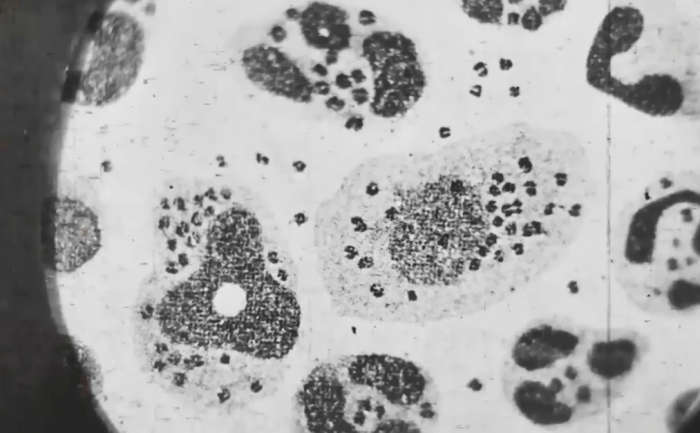

Врачи не могли понять, чем болен знаменитый плакатист. Правильный диагноз ему так и не смогли поставить. Во всяком случае пока он был жив. В официальных документах указано, что пациент умер от токсической формы чумы. Вскрытием руководил академик Николай Краевский. Он позволил присутствовать при этом своему приятелю из Ленинграда, 75-летнему патологоанатому.

Да это, батенька, variola vera – черная оспа,

- сказал гость столицы, лишь мельком взглянув на распластанное на столе тело.

Почему так? Причин немало. В книге "Путь хирурга. Полвека в СССР. Воспоминания" врач Владимир Голяховский объясняет, что большинство инфекционных диагнозов медперсоналом Боткинской были сразу отброшены. Перед поездкой за границу Кокорекин, как и любой другой человек, должен был сделать все необходимые прививки. И справка о полном курсе вакцинации у плакатиста действительно была. Однако позже выяснилось, что документ является подделкой. Художник опасался, что вакцины негативно скажутся на его ...ной жизни, ведь жена молода и красива, а ему уже за 50.

Второй причиной стала убеждённость советских медиков о полной победе над оспой. Регулярная вакцинация детей и взрослых позволяла им оставаться здоровыми, несмотря на единичные случаи заражения на окраинах страны. Тему оспы проходили в медвузах, но врачей, которые в своей практике видели бы больных с этим диагнозом, было не так уж много. Пожилой патологоанатом потому и смог быстро и точно установить причину смерти, потому что не раз сталкивался с пациентами, заразившимися оспой. Вспышка в Москве